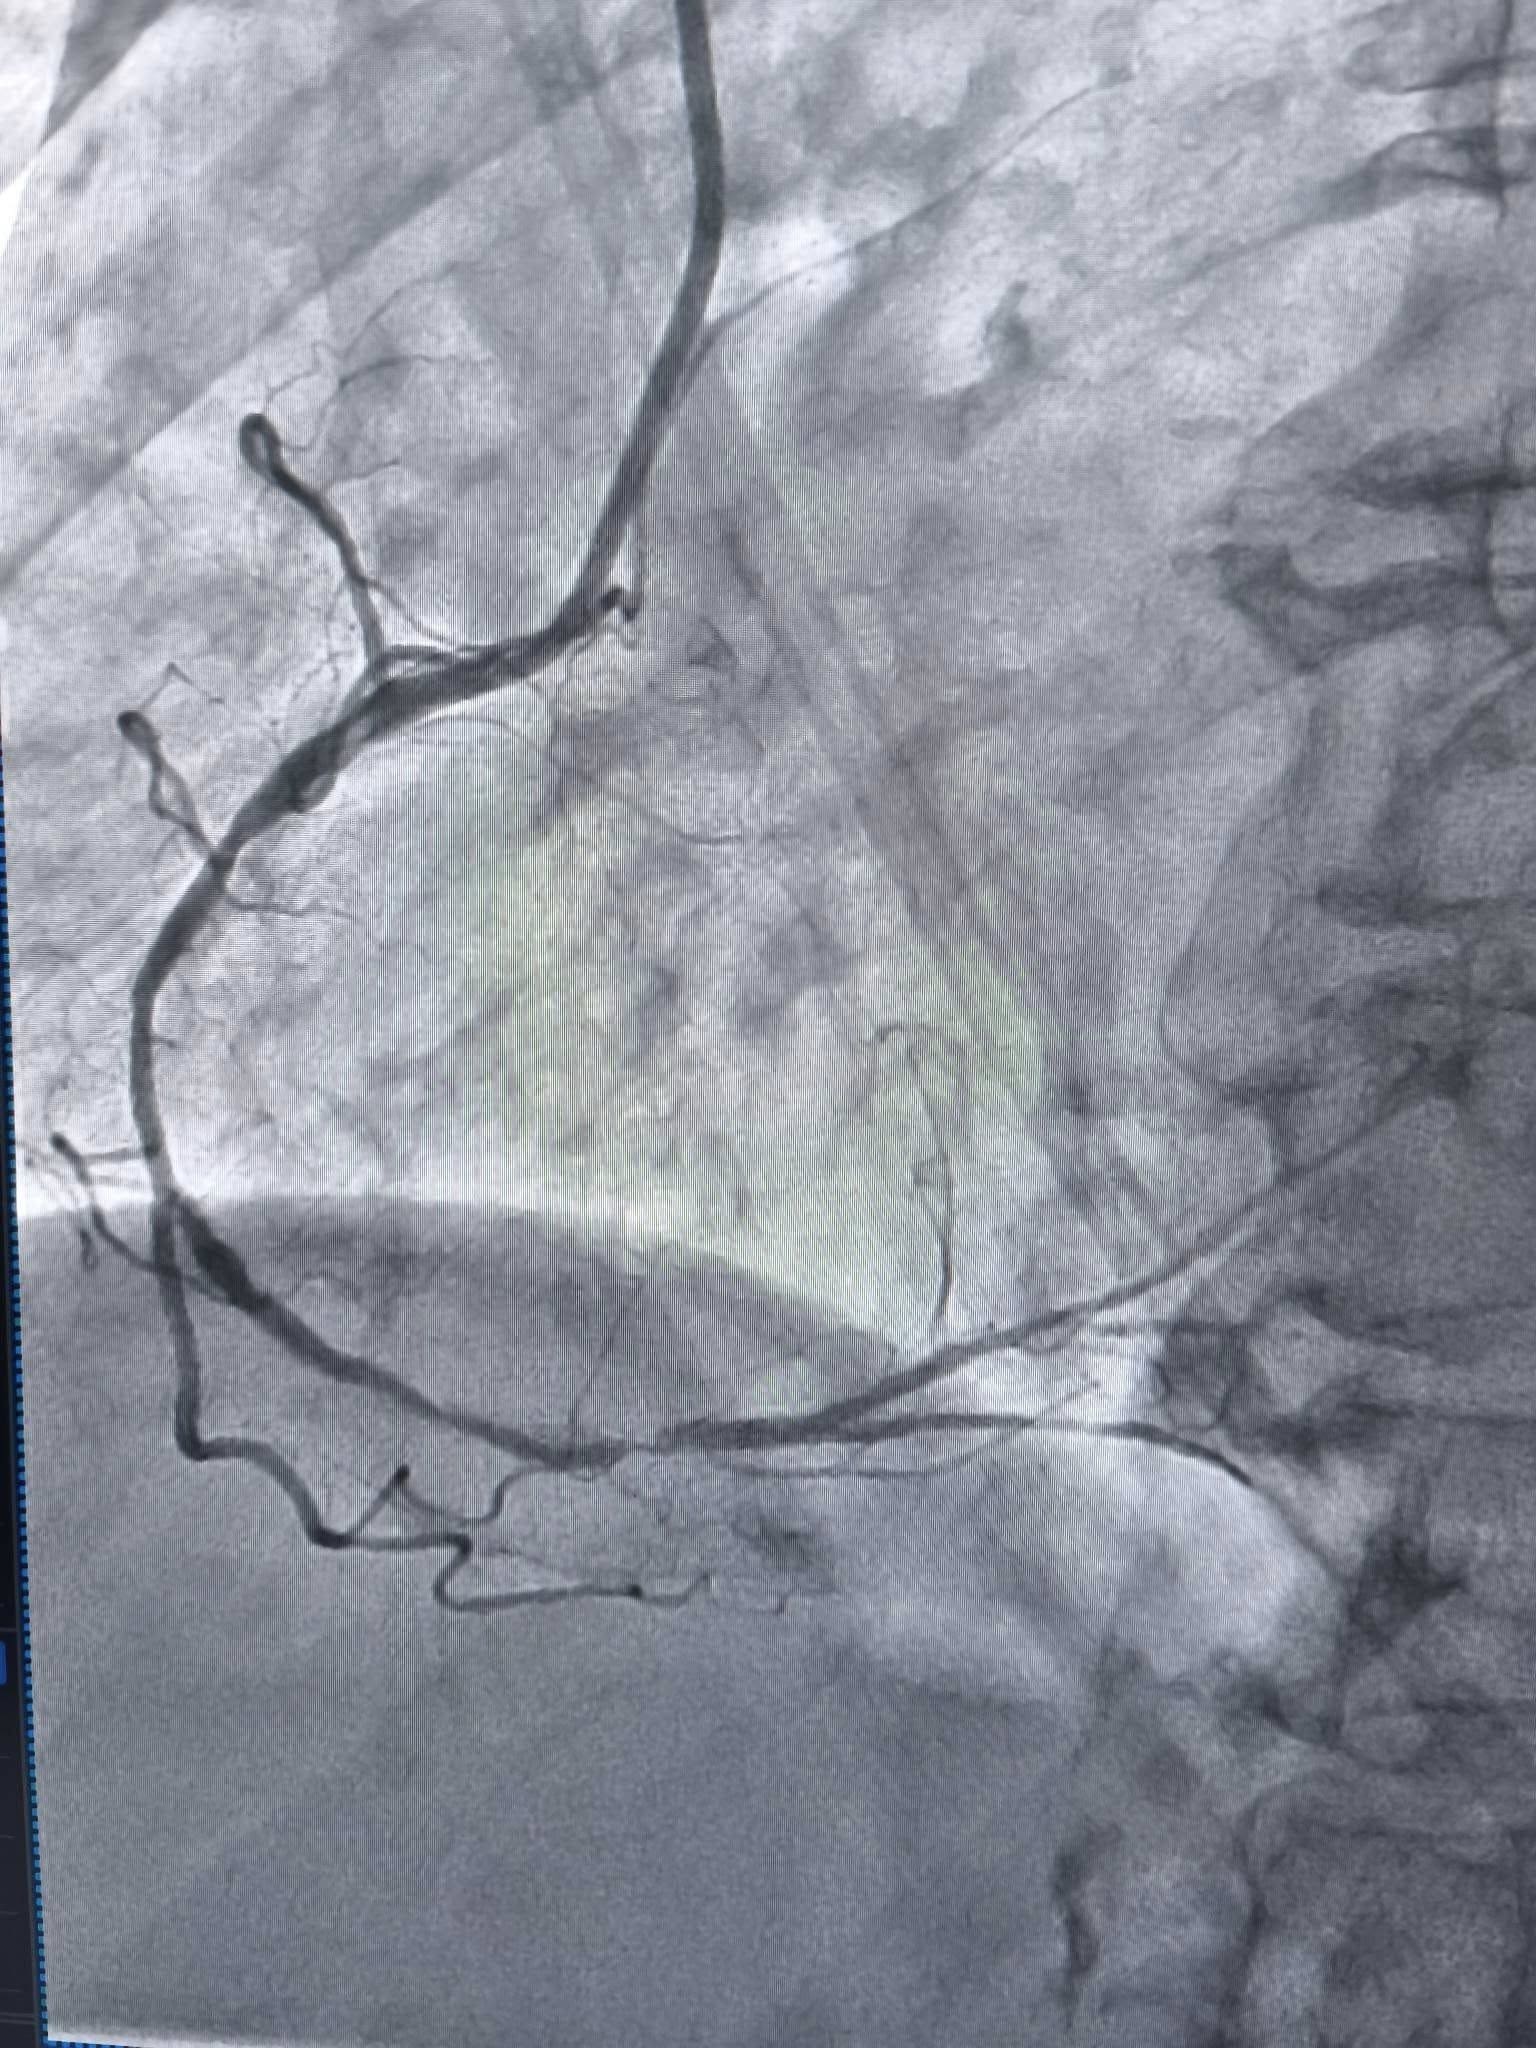

Пацієнтка потрапила до лікарні зі значним звуженням правої коронарної артерії. Ситуація була критичною: через виражений кальциноз (відкладення солей кальцію) судина стала настільки твердою, що стандартні методи розширення виявилися безсилими.

За словами завідувача відділення інтервенційної радіології та кардіології Богдана Маслія, лікарі намагалися розширити судину балоном під тиском 25 атмосфер. Для порівняння: це у 10 разів більше, ніж тиск у колесі автомобіля, проте навіть така сила не змогла подолати опір кальцію.

Єдиним виходом стало застосування ротаблятора – пристрою з крихітним буром, що має діамантове напилення.

- Після «шліфування» лікарі отримують можливість безперешкодно встановити стент, який відновить нормальний кровотік.